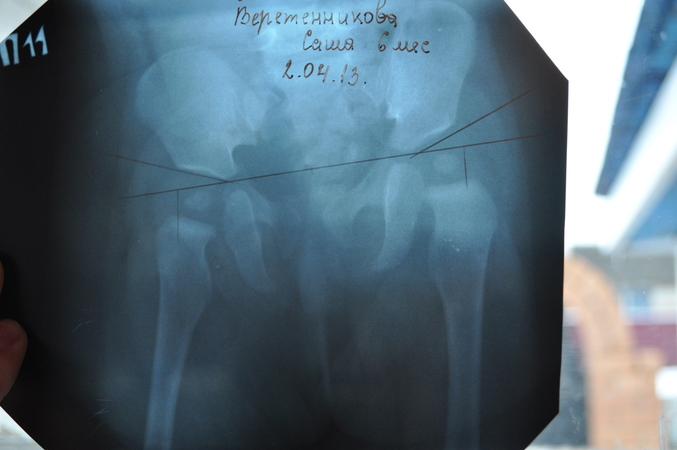

ОртопедияУже писала здесь , что в 3 мес моей дочке поставили легкую степень дисплазии. А в почти 6 мес поехали проверяться снова. Никакой дисплазии нет, но с левой ножкой явно что-то "не то", т.е. весь таз как-то перекосабочен, это видно даже на снимке, левая ножка немного короче кажется. Ацетабулярный индекс 25 градусов с обеих сторон. Но ортопед не смогла разобраться что же все таки не так.

Вот снимки в двух проекциях, хорошо видно ,что таз неровный, причем замечу ,что УКЛАДКА НОГ ПРАВИЛЬНАЯ и снимок держу ровно!